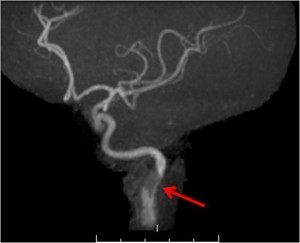

MRI for carotid artery imaging

MRI or rather MRA (MR-Angiography) is a non-invasive alternative for imaging the carotid arteries. MRA offers a three dimensional image of the carotid arteries without exposing the patient to ionizing radiation (although gadolinium is needed). The technique is called ‘time of flight‘.

MRI tends to overestimate the degree of stenosis as compared with direct arteriography. When comparing with angiography, different MRI techniques have varying degrees of sensitivity and specificity for detecting severe carotid artery stenosis. The values are 87-95{8ceaa46882e4d49283ff23b35262537230ad541262f55a031ead545e66522058} for sensitivity and lower for specificity (46-100{8ceaa46882e4d49283ff23b35262537230ad541262f55a031ead545e66522058}).

Limitations of MRI for carotid imaging:

- Patient movement reduces image quality – MRI is a rather long scan. Every movement including artery pulsations or swallowing motion reduce the quality of the images.

- MRI acquires better images when the blood flows in a laminar fashion. Therefore, stenosis reduces MRI image quality. This ‘signal dropout’ has been suggested as a serrogate for stenosis, but is unreliable.

- MRI can not distinguish between complete occlusion and hairline flow. Imaging ‘pseudo-occlusion’ can arise. It is also important to note that the ascending pharyngeal artery may seem like blood flow in the carotid – this artifact should be avoided.

- Tortuous vessels are also problematic for MRI.

- MRI is problematic with metallic stents.